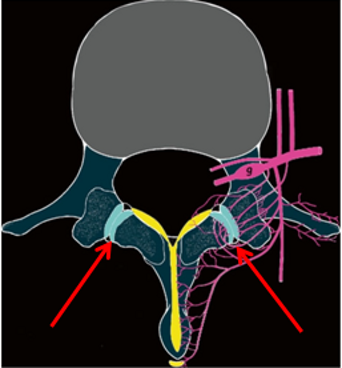

Tali strutture, che si trovano nella pozione posteriore di ciascuna vertebra, hanno una parte attiva nel movimento della colonna vertebrale.

Quando dolore lombare o degli arti inferiori origina da una degenerazione delle faccette articolari, si parla di sindrome delle faccette articolari lombari (sindrome faccettale lombare, lumbar facet joint syndrome).

Il trattamento è correlato strettamente all’etiologia della percezione del dolore in tutti casi di sindrome delle faccette articolari lombari: il nervo attraverso il quale viene percepito il dolore è la radice dorsale, ramo del nervo spinale (prevalentemente le branche mediane).

Questo nervo porta essenzialmente stimoli nocicettivi e non provvede a innervazione di muscoli o a trasmissione di stimoli tattili.

Neutralizzare questo nervo significa eliminare il dolore in una sindrome delle faccette articolari.